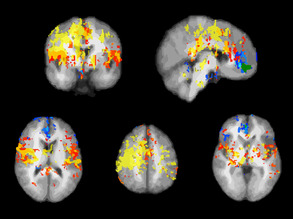

Comet Trails